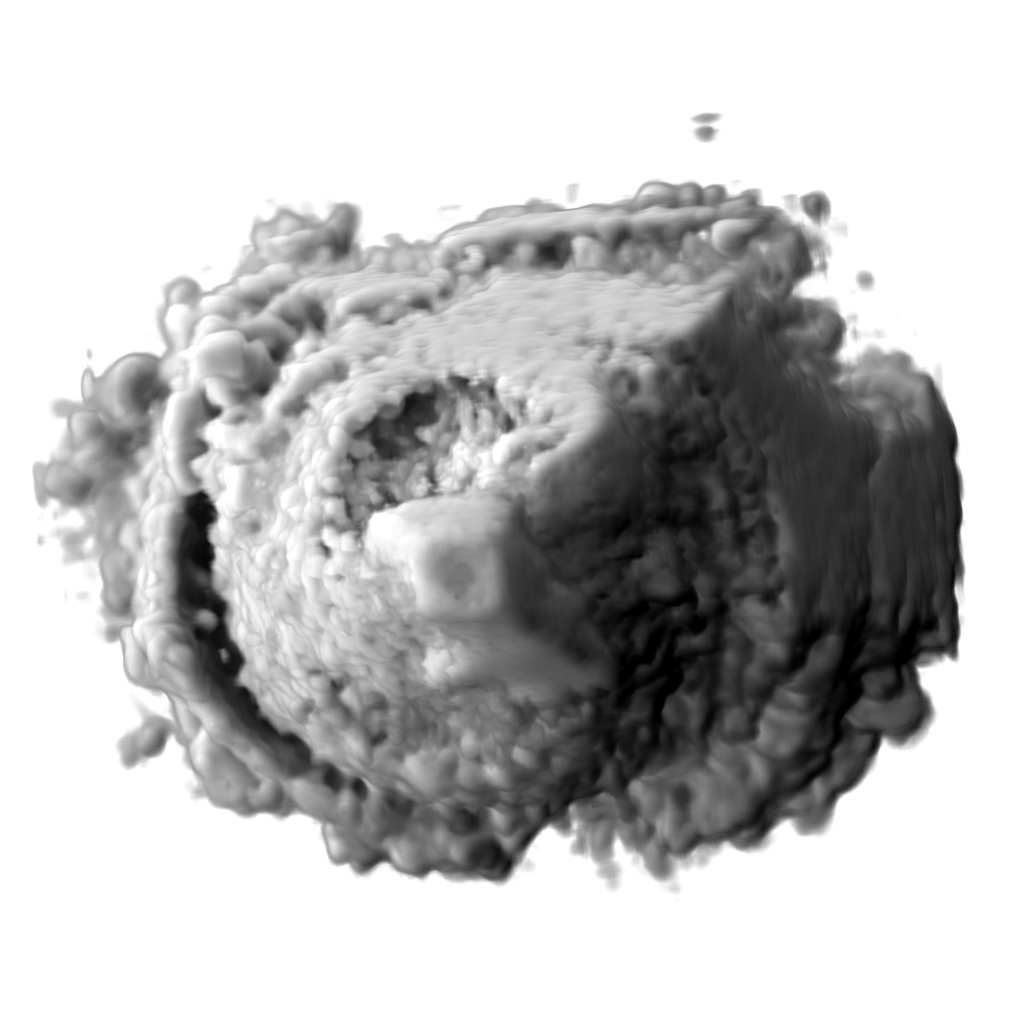

To increase robustness of the ultrasound segmentation, the various approaches are usually tailored for specific anatomies. Carneiro et al. have developed an automatic technique for segmenting the brain of a fetus carneiro08 . By first detecting the cerebellum, the system can narrow down the search for other features. On the other hand, segmentation is an extremely critical procedure which may obscure diagnostically relevant aspects of the anatomy under examination. Consequently, fully automatic segmentation techniques have not been implemented in clinical systems so far, with the exception of a method for follicle volumetry deutch09 , as shown in figure 3.

Feature extraction can be computationally costly. In-vivo 3D ultrasound examination cannot always afford the extra time necessary to extract the interesting structures. Therefore clipping is commonly used tool in live visualization of 3D ultrasound. Interactively removing regions which are not interesting, the user gets a clear view of the features normally occluded. Sakas et al. developed a clipping tool in their ultrasound visualization system sakas95 which is nowadays a standard feature in commercial 3D ultrasound systems. The user can in-vivo segment the dataset using three approaches. Drawing on one of the three axially-aligned slices, selecting everything along the current axis and within the sketch. Another tool is based on sketching directly on the 3D rendered scene. Each voxel is the projected onto the screen and removed if it lies within the marked area. The third clipping tool is based on the distance from a single mouse-click on the view-plane. A hemispherical wave front is propagated from the seed-point and stops when the voxels reach user-specified threshold. Figure 4 show an example of clipping implemented in the GE Voluson machines magicut99 .